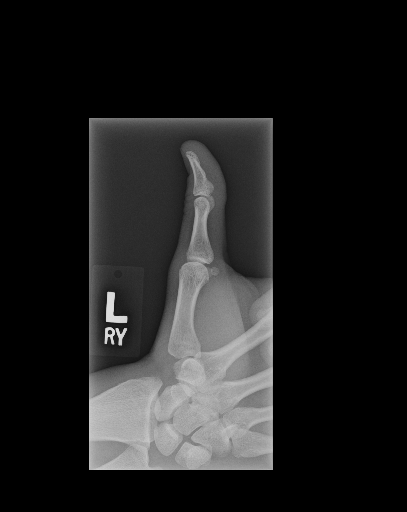

The first step in our pipeline is to detect the X-ray image carrier in the image. To this end, we apply OpenCV’s contour detection using Otsu binarization [14], and retrieve the minimum size bounding box, which does not need to be axis-aligned. This works sufficiently well as long as the majority of the image carrier is within the image (cf. Figure 3). However, the approach might fail for heavily tilted images or those where larger parts of the image carrier reach beyond the image border.

Hand Localization

To further improve the detection of hands, and in particular split the images where two hands are depicted on one image, we manually labeled approximately 150 bounding boxes in the images. Using this small dataset, we fine-tune a pre-trained single shot multibox detector (SSD) [12] with MobileNet as taken from TensorFlow. An exemplary results can be seen in Figure 3.